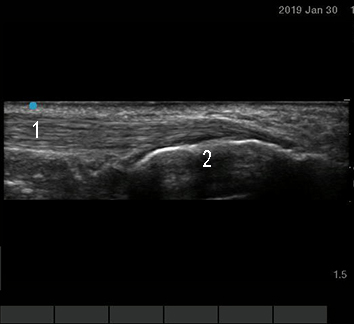

Foot & Ankle Achilles Tendon Longitudinal Image

Achilles

Calcaneus